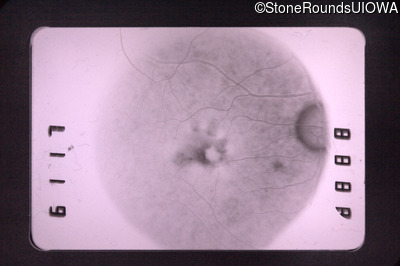

Fluorescein Angiography - Right - 20/40 -2

Exemplar